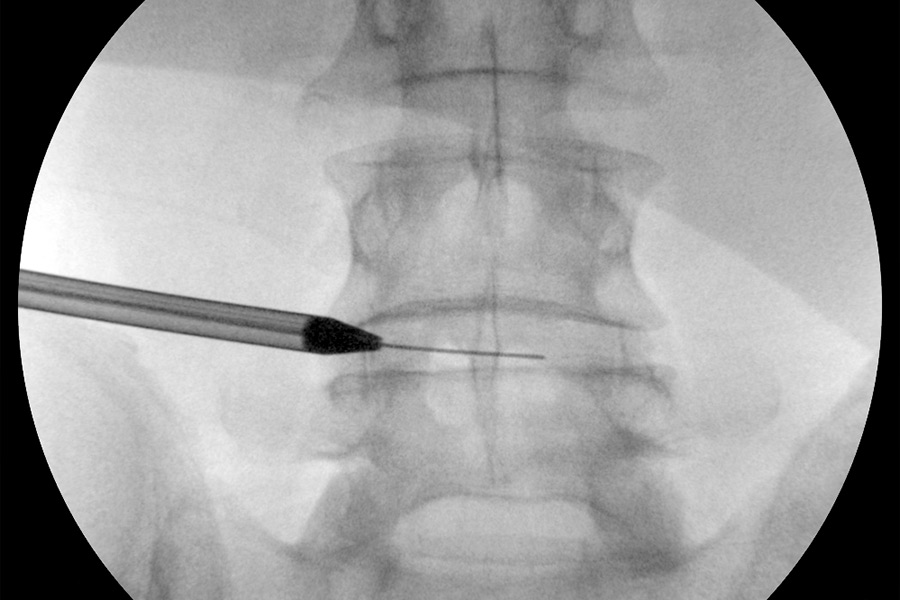

Se opta por el abordaje transforaminal accediendo hasta el canal. En el vídeo se puede apreciar la hernia discal que asoma debido a que no está en su ubicación natural, por lo que no están estructuradas las fibras del disco.